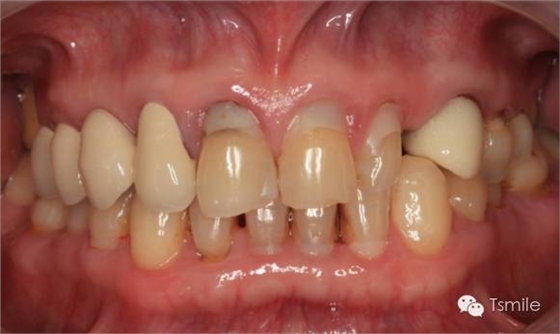

牙列重度磨耗的患者,特別是全牙列重度磨耗的患者,其口腔美觀和功能都受到了嚴(yán)重影響?;颊卟粌H需要口腔美學(xué)重建,還需要口腔功能的重建。

例如面對(duì)一個(gè)牙列重度磨耗的美學(xué)修復(fù)患者,我們首先根據(jù)患者主訴和美學(xué)檢查形成美學(xué)設(shè)計(jì),然后通過(guò)數(shù)碼圖像表達(dá)美學(xué)設(shè)計(jì)思想,制作診斷蠟型,口內(nèi)制作診斷飾面,更加真實(shí)地表達(dá)美學(xué)設(shè)計(jì)。根據(jù)患者的要求和口內(nèi)試戴情況調(diào)改診斷飾面,最終確定美學(xué)修復(fù)設(shè)計(jì),即最終修復(fù)體的各種美學(xué)參數(shù)。接下來(lái)就是美學(xué)實(shí)現(xiàn)過(guò)程,在診斷飾面上進(jìn)行精確地牙體預(yù)備,制取印模和工作模型,技師按照最終診斷飾面的形態(tài)、大小和排列制作最終美學(xué)修復(fù)體,最后完成修復(fù)體粘接。